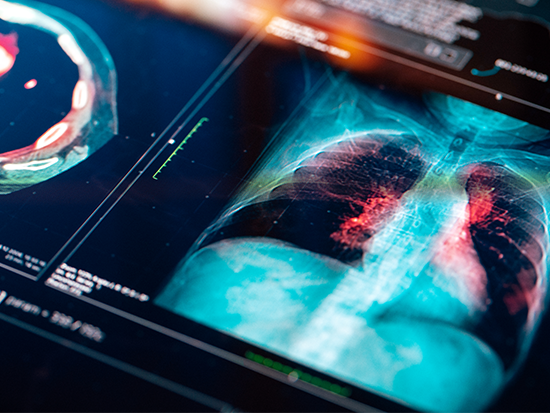

Computed Tomography

Master medical imaging techniques, radiation safety, and prepare for certification in our Computed Tomography program, positioning yourself for a rewarding career as an MRI tech, CT tech, nuclear medicine technologist, or radiologic tech in hospitals and imaging centers.